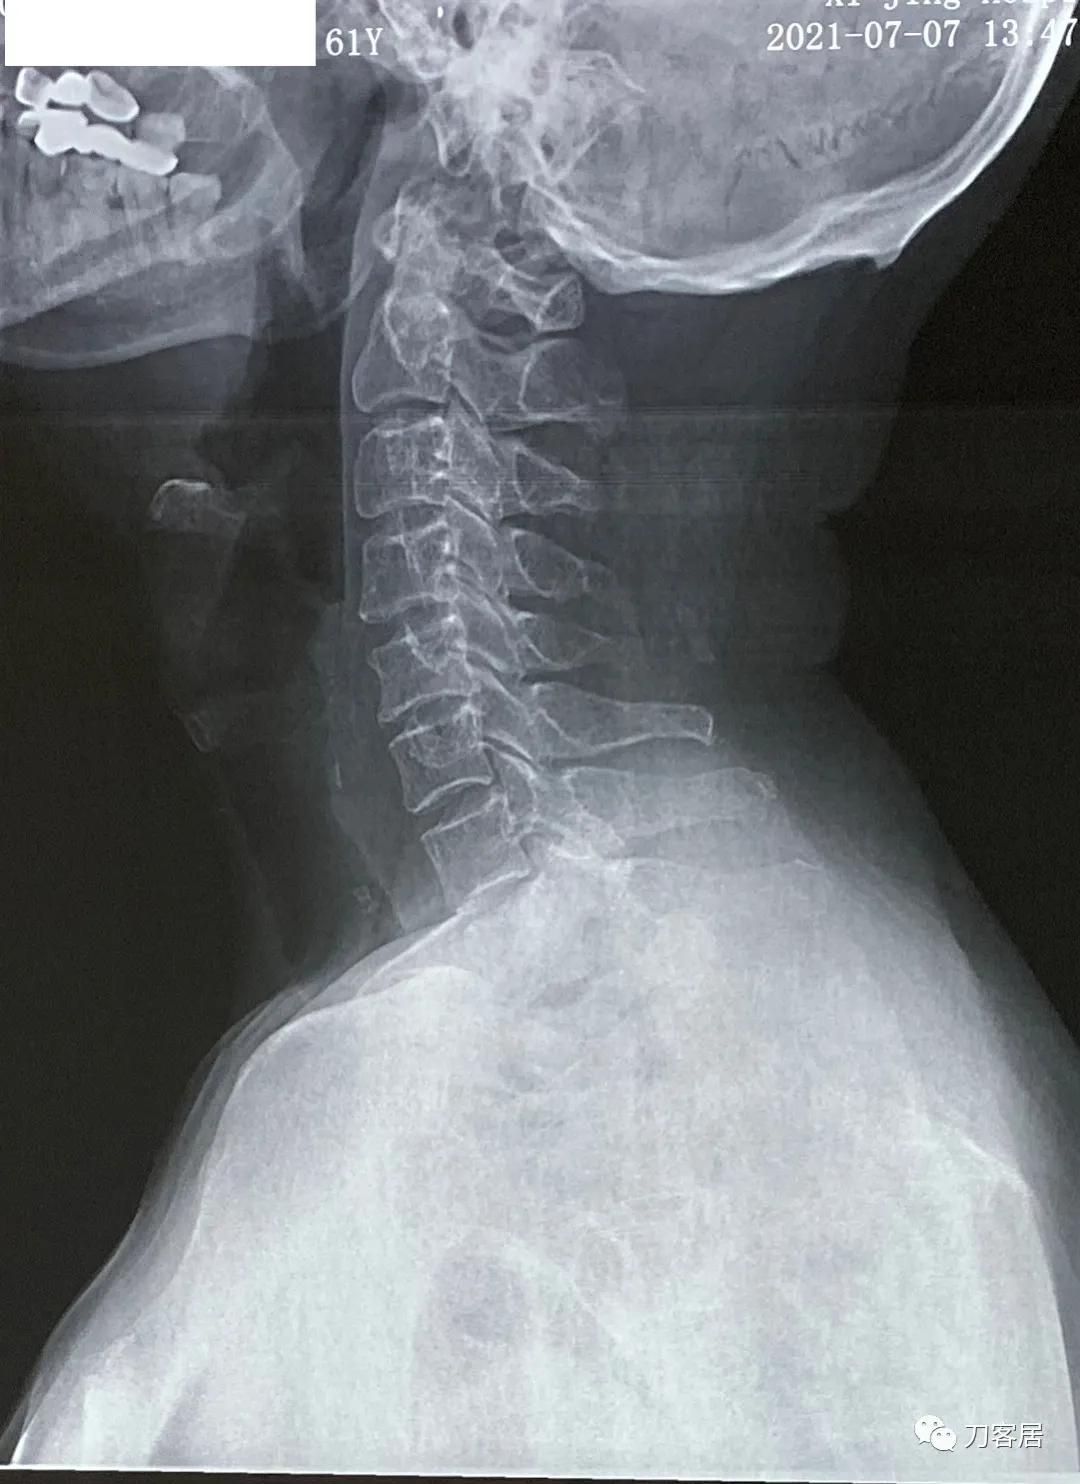

图8. 20210721颈椎侧位X线片,颈椎曲度尚好。